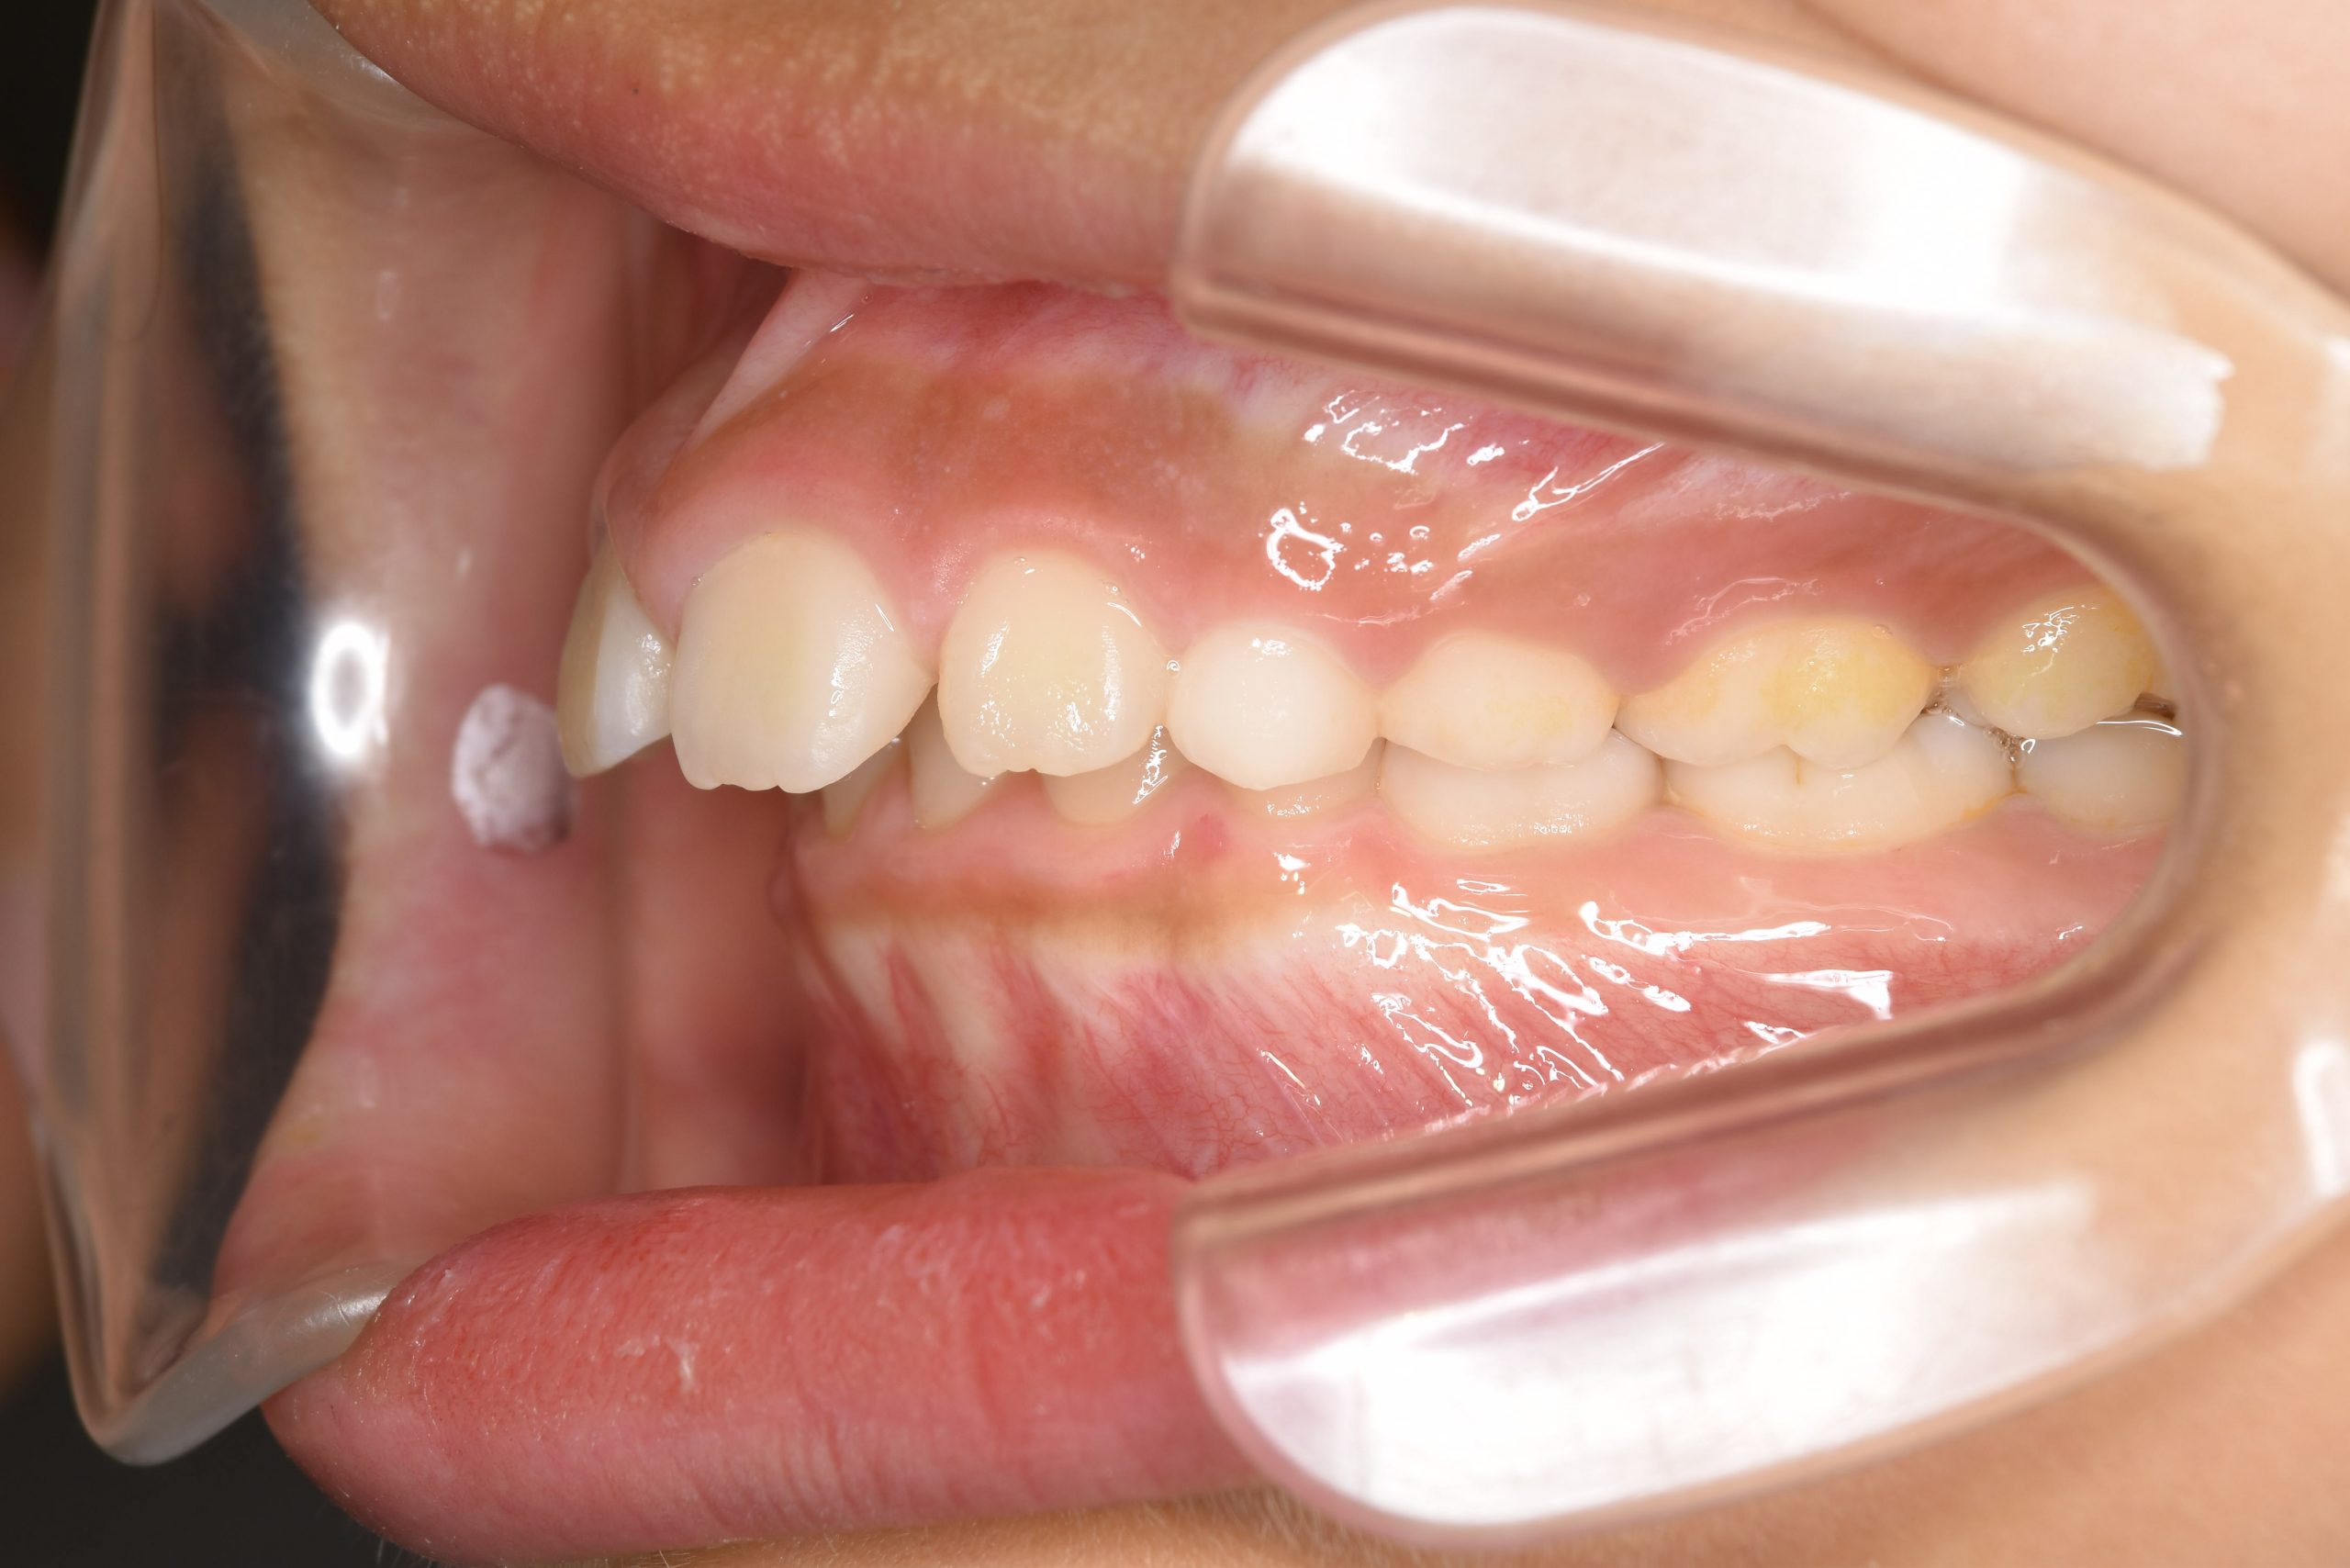

アフター

子どもの矯正治療|症例_547

施術内容 上顎急速拡大装置と下顎リンガルアーチを用いて上下顎骨を拡大した。

その後マウスピース型矯正装置で歯牙を配列し良好な咬合を獲得した。

治癒期間 2年10か月